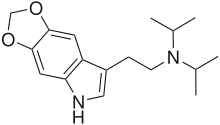

| 4,5-MDO-DMT | artificial | 4,5-(OCH2O) | CH3 | CH3 | 2-(2H,6H-[1,3]Dioxolo[4,5-e]indol-8-yl)-N,N-dimethylethan-1-amine | 81249-30-1 |

| 4,5-MDO-DiPT | artificial | 4,5-(OCH2O) | CH(CH3)2 | CH(CH3)2 | N-[2-(2H,6H-[1,3]Dioxolo[4,5-e]indol-8-yl)ethyl]-N-(propan-2-yl)propan-2-amine | 82173-82-8 |